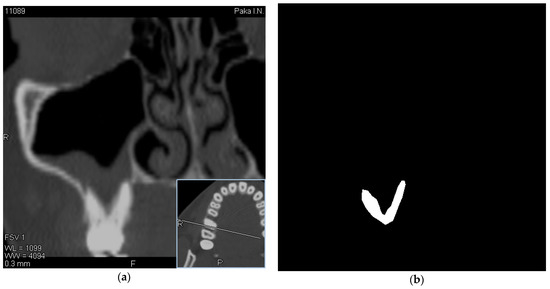

In this regard, along with the evaluation of MSCT images, we also evaluated the history and examination data of these patients obtained using a chatbot, which can significantly increase the information content of diagnostic procedures and become the basis for making the correct diagnosis. The visualization of data was performed using the RadiAnt [21] software. Experts selected tomographic images with a visible location of the roots of the teeth in the maxillary sinus. Images have been obtained using a Toshiba Aquilion 4, Computed Tomography Scanner (Japan) with a scan thickness of 2 mm [22]. An example of OMS data as well as a mask created by an expert is shown in Figure 1.

Figure 1. Sample CT image and its manual segmentation label (a)—initial image, (b)—mask created by expert.